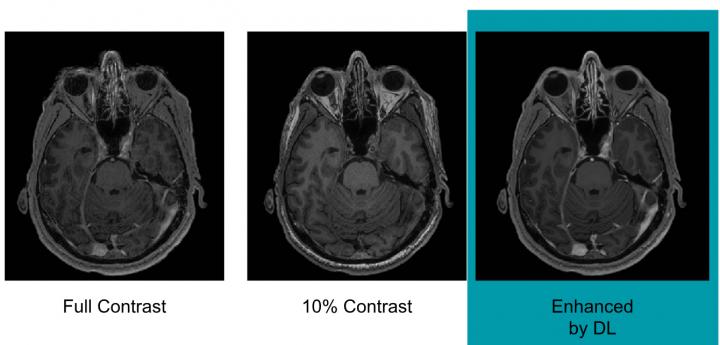

To train the deep learning algorithm, the researchers used MR images from 200 patients who had received contrast-enhanced MRI exams for a variety of indications. They collected three sets of images for each patient: pre-contrast scans, done prior to contrast administration and referred to as the zero-dose scans; low-dose scans, acquired after 10 percent of the standard gadolinium dose administration; and full-dose scans, acquired after 100 percent dose administration.

The algorithm learned to approximate the full-dose scans from the zero-dose and low-dose images. Neuroradiologists then evaluated the images for contrast enhancement and overall quality.

Results showed that the image quality was not significantly different between the low-dose, algorithm-enhanced MR images and the full-dose, contrast-enhanced MR images. The initial results also demonstrated the potential for creating the equivalent of full-dose, contrast-enhanced MR images without any contrast agent use.

These findings suggest the method's potential for dramatically reducing gadolinium dose without sacrificing diagnostic quality, according to Dr. Gong.